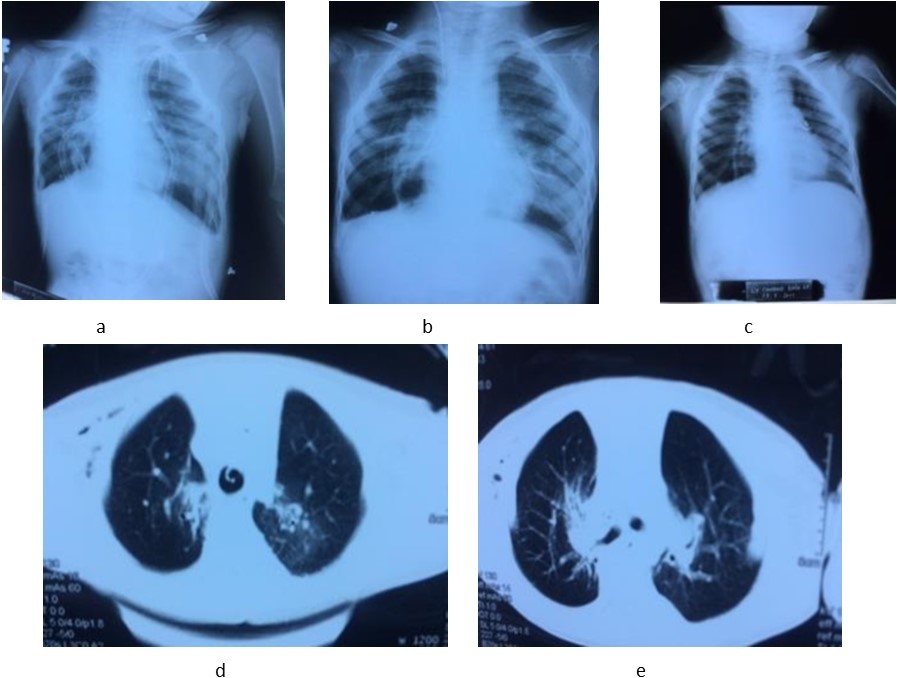

Early outcome: After the operation, the patient was ventilated via endotrachial tube, controlled the status of respiration, hemodynamics and draignage care. Recipient was weaned off ventilator in 36 hours. Postoperative immunosuppression consists of triple drug therapy with neoral, cellcep, and prednisolone. We judge acute rejection on the clinical, radiographic fndings, other subclinical tests and control opportunistic infection. At 1, 3, 6, 9 and 12 months after LDLT, the recipient has recovered lung function very fast and there were not any early complications and adverse events after the operation. Now the recipient had normal physical exercise capacity, subclinical tests in normal limits and not respiratory symptoms, opportunistic infection and no evidence of rejection. (Image 2)

Image 2.The chest X-ray images at the first (a), 7th day (b) and 12th month (c). CT-scan images at the 3th day (d) and 8th day (e) after lung transplantation.

In recent years, the number of lung transplantation patients has increased remarkbly with the trend to bilateral lung transplantation more than single lung transplantation. The sources of donors are extended, with non-heart beating donors, ex-vivo lung perfusion and living donors. LDLT is a last option chosen to save critically ill patient with end-stage pulmonary disease who cannot wait for organs from cadaveric donor4. In our receipient, the indication of lung transplantation was resonable because he always had recurent respiratory infection, decreased PaO2, increased oxygen requirements, hypercapnia, pulmonary arterial hypertension. Two donors were relative and young. The anatomic and functional size matchings between the receipient and two donors played a very important role in the success of this lung transplantation case. We use a formula to estimate graft FVC (Forced vital capacity) on the basis of the donor’s measured FVC and the number of pulmonary segments being implanted4. The right lower lobe FVC of uncle estimated 0.71 (L), the left lower lobe FVC of father estimated 0.8 (L), the receipient FVC estimated 0.98 (L). Total FVC of the two grafs/ FVC of the recipient was 1.5 (according to the Japanese authors, it is acceptable when this ratio > 0.45). Therefore, after vetilation these 2 lung lobes expanded nearly completly with the size of the paient’s chest cavity and by the 7th day, both 2 lung lobes had expanded completly. At the 1st, 3th, 6th , 9th and 12th month, the chest X-ray image are normal. The clinical change of the recipient: fever immediately after operation and recovered in 2 days, sputum in 5 days, oxygen therapy in 5 days; weaned off ventilator in 36 hours. After 4 days, he was withdrawn from thoracic drainage and could walk himself in the room at the 6th day after the operation. In the 1st, 3th, 6th, 9th and 12th month, he had normal physical activities, not any clinical symptoms (now he returns to school and takes part in all activities as his classmates), subclinical tests in normal limits and no evidence of opportunistic infection or rejection.